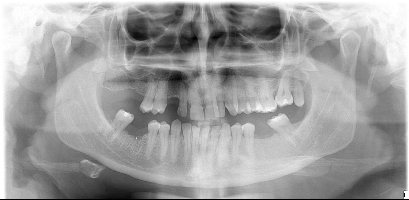

Buonasera scrivo per avere maggiori dettagli (opinioni specialistiche )sulla mia situazione non facile é da tempo che avverto dolore a dei dent,i caso strano la notte dormo specifico non mi sveglio per il dolore che al contrario mi accompagna nell'arco della giornata ad intervalli più o meno intensi inserisco la mia ortopanoramica . Saluti

chicca.jpg

[ 51.31 KiB | Osservato 2019 volte ]